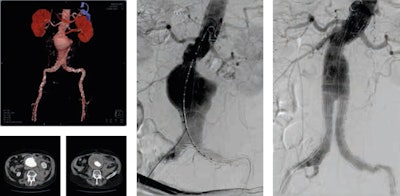

He thinks retroperitoneal hematoma adjacent to an abdominal aortic aneurysm is the most common imaging finding indicative of aneurysm rupture. Endovascular aneurysm repair (EVAR) has become an established technique for the treatment of many infrarenal aortic aneurysms. Less invasive than open surgical repair, EVAR is associated with better outcomes, according to Pyra (see figures 1 and 2).

Rare findings, such as arteriovenous malformations, are extremely challenging and require accurate diagnosis and appropriate treatment, especially if they are high-flow and/or extensive lesions. Embolization with coils and 98% ethanol is just one of the many existing treatment possibilities (see figure 3).